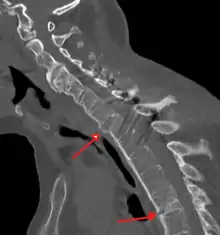

Fracture of the T5 and C7 vertebra due to trauma in a person with ankylosing spondylitis as seen on a CT scan

Prognosis is related to disease severity.[9] AS can range from mild to progressively debilitating and from medically controlled to refractory. Some cases may have times of active inflammation followed by times of remission resulting in minimal disability while others never have times of remission and have acute inflammation and pain, leading to significant disability.[9] As the disease progresses, it can cause the vertebrae and the lumbosacral joint to ossify, resulting in the fusion of the spine.[48] This places the spine in a vulnerable state because it becomes one bone, which causes it to lose its range of motion as well as putting it at risk for spinal fractures. This not only limits mobility but reduces the affected person's quality of life. Complete fusion of the spine can lead to a reduced range of motion and increased pain, as well as total joint destruction which could lead to a joint replacement.[49]

Osteoporosis is common in ankylosing spondylitis, both from chronic systemic inflammation and decreased mobility resulting from AS. Over a long-term period, osteopenia or osteoporosis of the AP spine may occur, causing eventual compression fractures and a back "hump".[50] Hyperkyphosis from ankylosing spondylitis can also lead to impairment in mobility and balance, as well as impaired peripheral vision, which increases the risk of falls which can cause fracture of already-fragile vertebrae.[50] Typical signs of progressed AS are the visible formation of syndesmophytes on X-rays and abnormal bone outgrowths similar to osteophytes affecting the spine. In compression fractures of the vertebrae, paresthesia is a complication due to the inflammation of the tissue surrounding nerves.